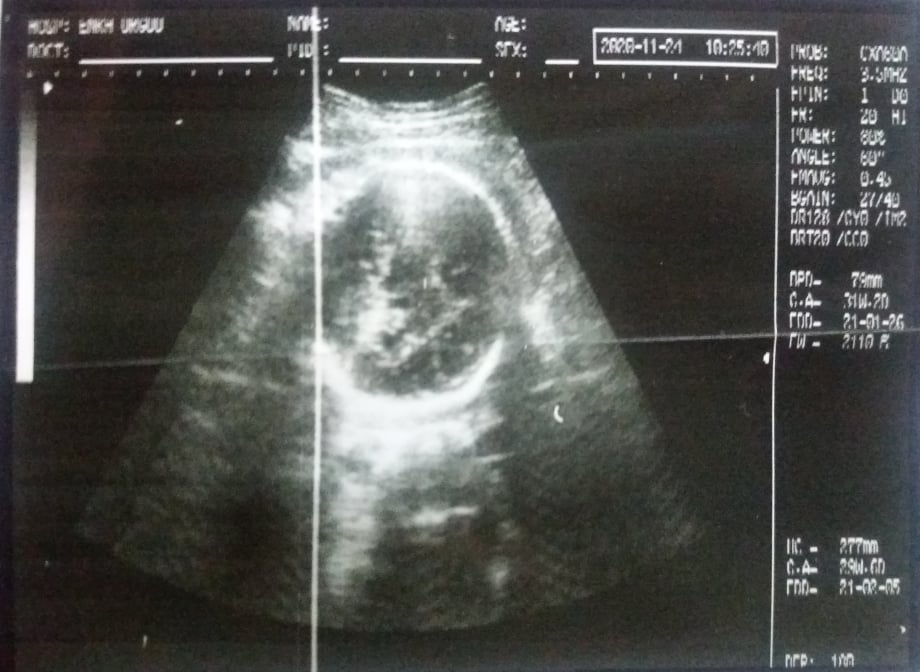

“Хэрвээ олуулаа нэг өрөөнд бужигнаж байгаад баригдвал 500 мянган төгрөг “тас” шүү дээ” гээд амны хаалтныхаа цаанаас намжирдаж байна. Ургийн ЭХО, дотор ЭХО бусад гээд шаардлагатай шинжилгээнүүдийг хийсээр нэлээд удлаа. Хоёр баяртай мэдээтэй гарч ирлээ. Эхнийх нь бидний хүүхэд өсөлт хөгжил сайн, сар хагасын хугацаа үлдсэн. Дараагийнх нь хоёр хоног бидний санааг зовоосон “ханиалга” корона биш даарснаас болсон ханиад болж таарав.Удахгүй мэндлэх хүүхдээ хүлээсэн догдлол, баяр, өдөр л 20, 30-аар нэмэгдэж байгаа коронавирусийн халдварт сэтгэл зовнисон айдас, түгшүүр цөм хавсрахаараа ямар сонин мэдрэмж байдаг юм бэ.